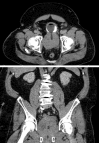

Lower urinary tract symptoms (LUTS) secondary to benign prostatic hypertrophy (BPH) are among the most common medical issues for aging men. Population-based studies suggest that 13.8% of men in their 40s and more than 40% of men over age 60 have BPH. When LUTS are refractory to medical therapy and bothersome enough to warrant surgical intervention, transurethral resection of the prostate and open simple prostatectomy have been the historical reference-standard procedures for decades. Both procedures are highly effective and offer durable improvements in urinary functional outcomes. However, they also have the potential for considerable perioperative complications and morbidity. In an effort to limit surgical morbidity, a variety of minimally invasive surgical techniques to treat BPH have been introduced. Herein we present a comprehensive, evidence-based review of the efficacy and safety profile of modern minimally invasive treatments for large-gland BPH.